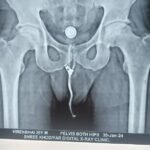

Hip replacements consist of multiple parts – the acetabular shell or socket is made of titanium which accommodates an inner insert made of highly cross-linked polyethylene. On the femoral side, the stem is made of titanium and can accommodate different sized ceramic heads. There is no metal on metal components as existed in previous designs.